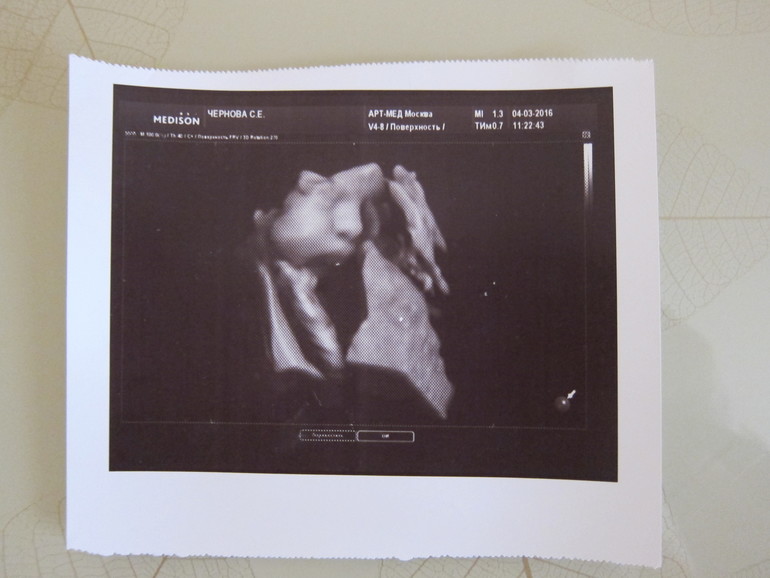

Ровно в 34 недели я опять на УЗИ (в уже ставшем любимом Арт-Меде), ездили всей семьей (с Димой и Ярославом), посмотрели нашу малышку, я шоке, там такая девочка серьезная… губы надуты, недовольная… но красивая))))))). А в целом - всё хорошо, мы весим 2 300 кг (ни маленькая, ни большая, средняя девочка), опять сказали, что длинненькая (Ярослав 59 см родился, прям жирафик), уже волосатенькая (прям волосики показали), носик явно не Димин (у Яси на УЗИ сразу было понятно, носик длинный и острый), единственный минус - у нас двойное не тугое обвитие , но в общем и целом ничего страшного, т.к. обвитие не тугое, у меня Яся тоже с 2-м обвитием родился. Лежит правильно - головкой вниз, личиком к моей спине, но я это чувствую, прям попку можно руками нащупать. Ярослава она уже обожает, если он плачет, она там вся извивается, и чувствуется, что очень переживает))), а когда я его обнимаю, она его через животик гладит (прям, не пихает, а гладит))).